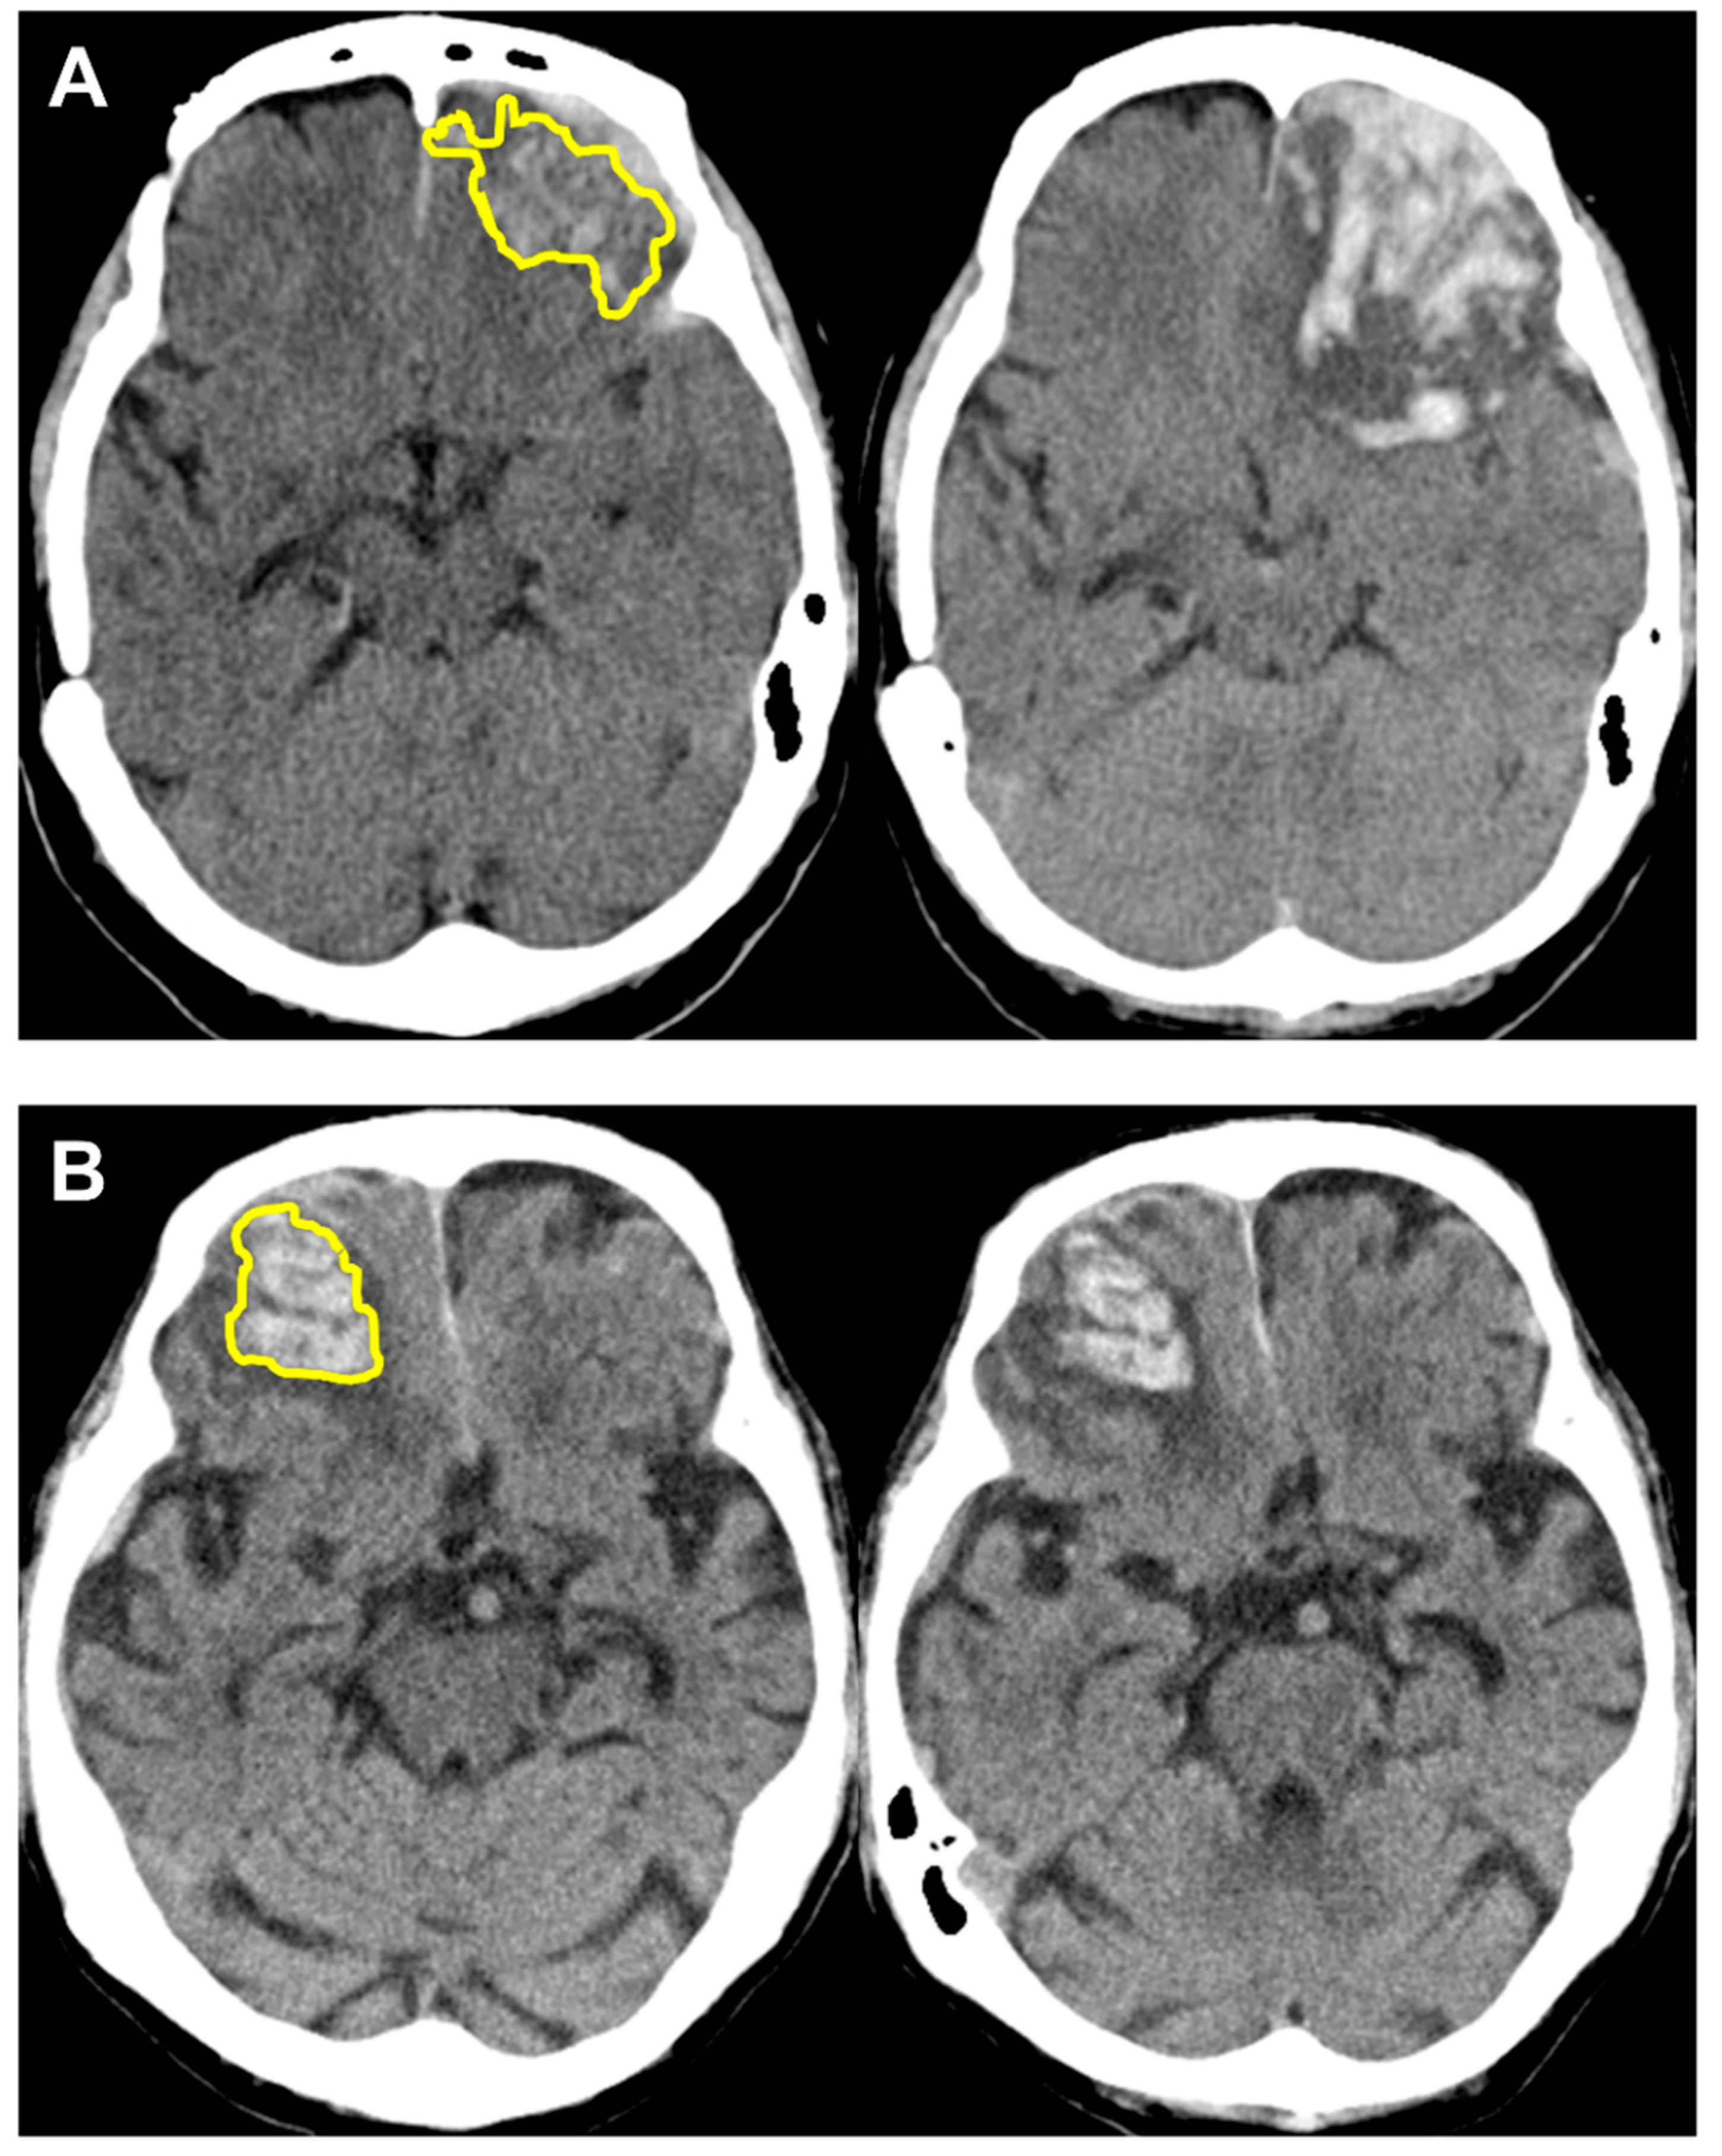

3.3. Performance of Radiomics Score with Case Examples